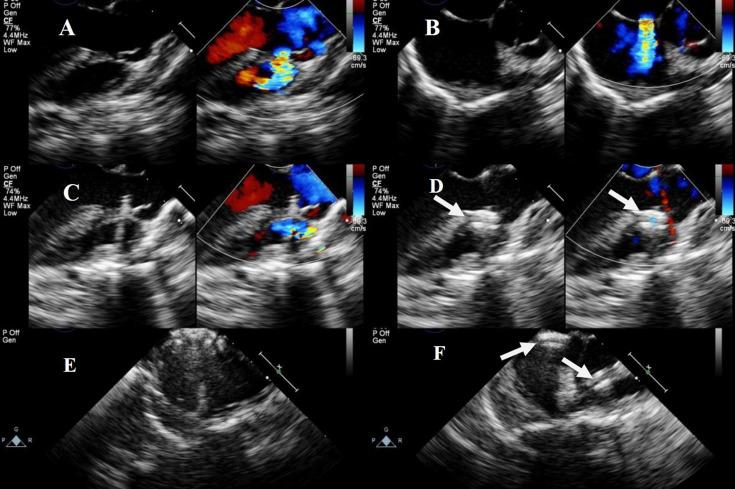

Ventricular septal defect (VSD) with atrial septal defect (ASD) is a common complex congenital heart disease. This study aimed to evaluate the clinical efficacy and safety of transesophageal echocardiography (TEE)-guided percardiac or combined percutaneous techniques for treating VSD with ASD in patients with varying anatomies.

This retrospective cohort study reviewed 40 cases of VSD with ASD treated in our center from June 2015 to July 2023. Under TEE guidance, peratrial, perventricular, or combined percardiac/percutaneous approaches were used based on the VSD type and secundum-type ASD. Follow-up examinations, including electrocardiography, transthoracic echocardiography, and X-ray, were performed after surgery at 24 hours, 1, 3, 6, and 12 months, and yearly.

All patients underwent surgery successfully (100%), with 24, 5, and 11 patients undergoing simultaneous closure via the peratrial, perventricular, and combined percardiac/percutaneous approaches, respectively. Among them, there were six cases of a mild residual shunt, three instances of a mild tricuspid regurgitation, two cases of a mild aortic valve regurgitation, one case of a mild mitral regurgitation, and three cases of an incomplete right bundle branch block, all observed after VSD closure; all had resolved within 6 months of the operation. The chi-square test showed no significant differences in adverse event rates among the three surgical approaches (χ = 0.09, = 2, = 0.957). The Friedman test compared the preoperative and postoperative left ventricular end-diastolic diameter for the three approaches, providing < 0.001, = 0.589, and = 0.445, respectively. None of the patients required reoperation during the follow-up period.

Under TEE guidance, using diverse percardiac or combined percutaneous device closure techniques for the one-stop treatment of different types of VSDs combined with ASD is safe, effective, and feasible. These approaches can be performed as a valuable alternative therapy for selected patients.